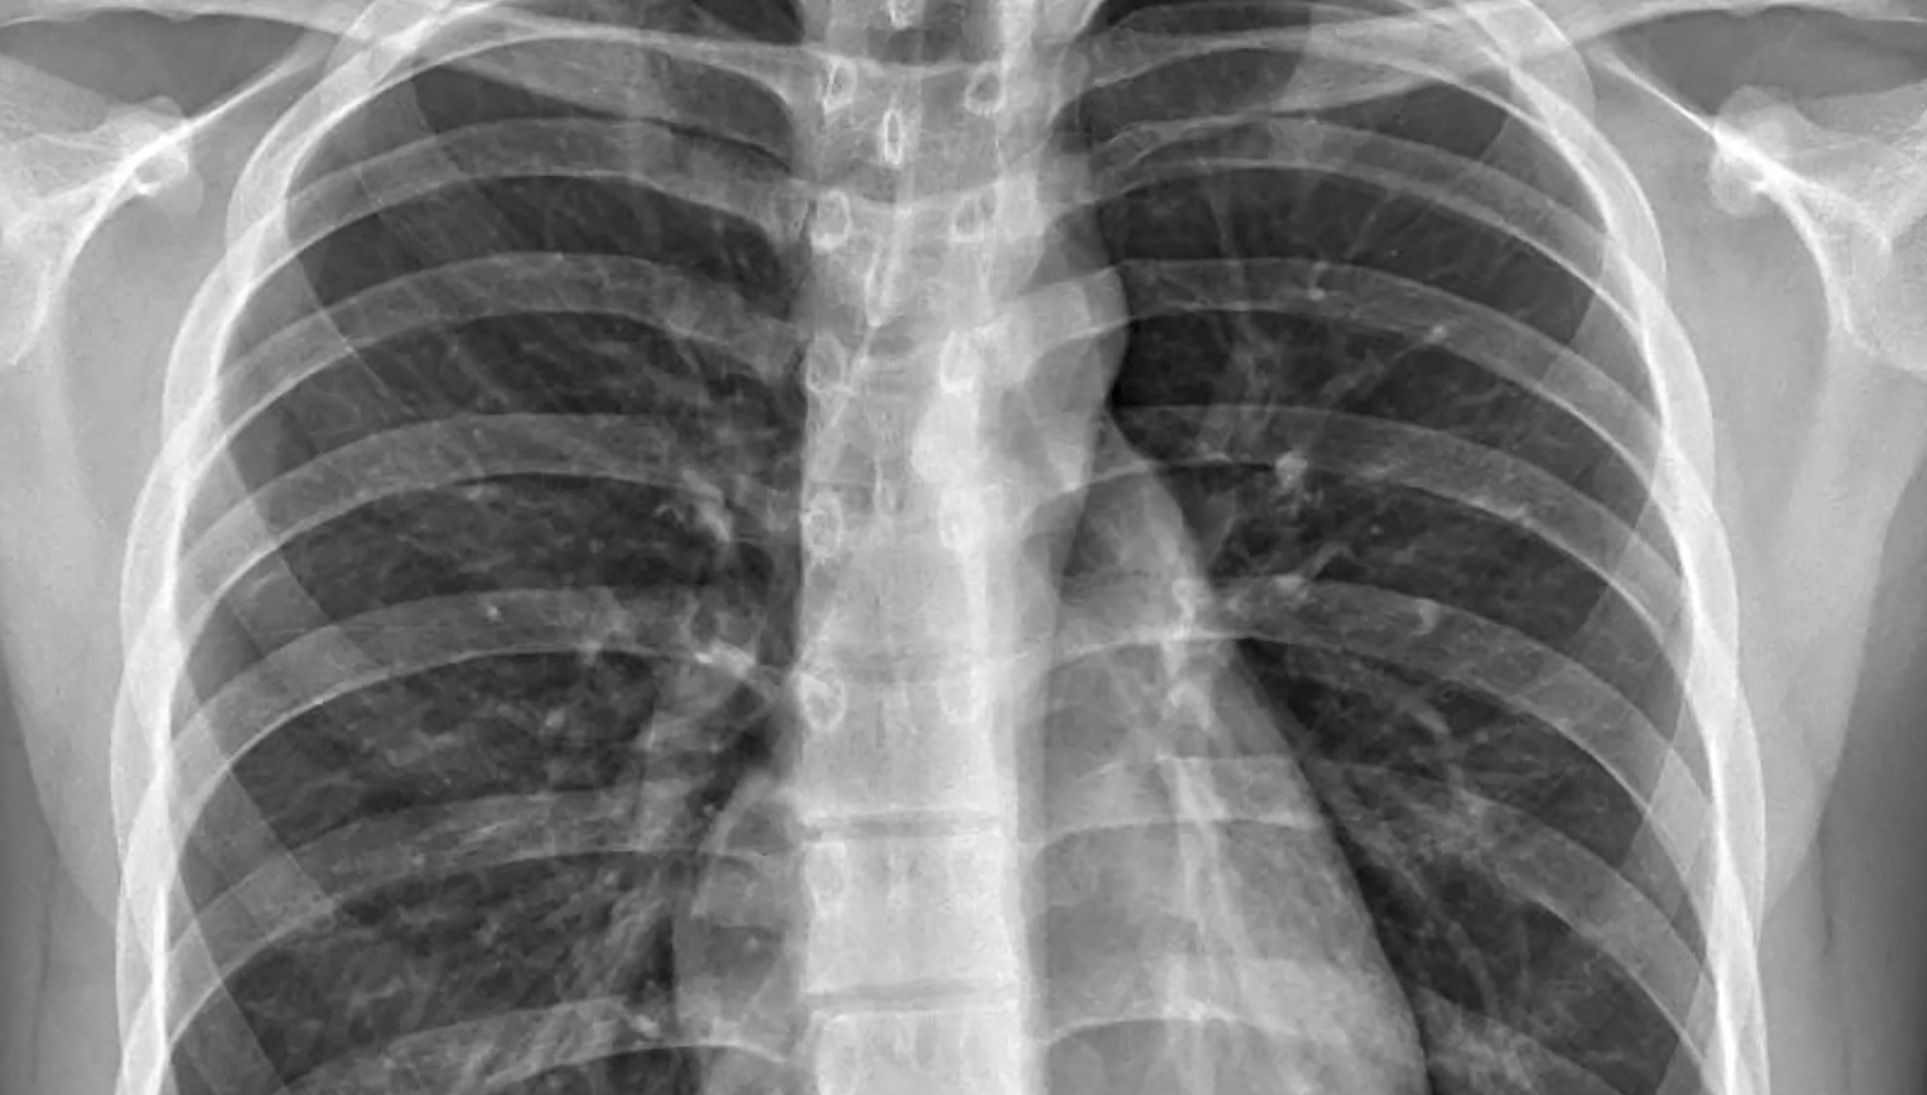

Quartz countertops, a staple in high-end kitchens, are composed of over 90% silica. When the stone is cut, polished, or ground, fine silica dust is released into the air. Workers who inhale these particles face significant health risks, including silicosis, a severe and often fatal lung disease.

Recent studies have exposed the alarming scope of the problem. For example, PEOPLE magazine reported on a study published in JAMA Internal Medicine, which analyzed 52 cases of silicosis among California workers fabricating quartz countertops. Of those cases, 10 workers have died, and three required lung transplants.

Marek, whose story was detailed in PEOPLE, worked for over a decade in countertop manufacturing, breathing in the "lethal dust" that ultimately cost him his health. Tragically, Marek is too ill to undergo a lung transplant, and his condition has rapidly deteriorated since his diagnosis.